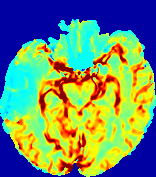

LesionRefer to captionRefer to captionRefer to captionRefer to captionRefer to captionRefer to caption𝐕rgbsubscript𝐕𝑟𝑔𝑏{\bf{V}}_{rgb}Refer to captionRefer to captionRefer to captionRefer to captionRefer to captionRefer to caption𝐕2subscriptnorm𝐕2{\|\bf{V}}\|_{2}Refer to captionRefer to captionRefer to captionRefer to captionRefer to captionRefer to captionRefer to caption3.53.53.52.82.82.82.12.12.11.41.41.40.70.70.70.00.00.0(mm/s)𝑚𝑚𝑠(mm/s)D𝐷DRefer to captionRefer to captionRefer to captionRefer to captionRefer to captionRefer to captionRefer to caption0.0200.0200.0200.0160.0160.0160.0120.0120.0120.0080.0080.0080.0040.0040.0040.0000.0000.000(mm2/s)𝑚superscript𝑚2𝑠(mm^{2}/s)Slice #1Slice #2Slice #3Slice #4Slice #5Slice #6

Figure 4: PIANO feature maps for another patient in the ISLES 2017 training set, where the lesion is located in the right hemisphere. Top row: segmented stroke lesion region (white) on different slices. The corresponding slices for the PIANO feature maps are shown in the following rows.

For a better insight into an estimated velocity field 𝐕𝐕{\bf{V}} and diffusion field 𝐃𝐃{\bf{D}}, we compute the following maps: (1) 𝐕rgbsubscript𝐕𝑟𝑔𝑏{\bf{V}}_{rgb}: Color-coded orientation map of 𝐕=(Vx,Vy,Vz)T𝐕superscriptsuperscript𝑉𝑥superscript𝑉𝑦superscript𝑉𝑧𝑇{\bf{V}}=(V^{x},V^{y},V^{z})^{T}, obtained by normalizing 𝐕𝐕{\bf{V}} to unit length and mapping its 3 components to red, green, blue respectively; (2) 𝐕2subscriptnorm𝐕2\|{\bf{V}}\|_{2}: 222 norm of 𝐕𝐕{\bf{V}}; (3) D𝐷D: scalar field in Eq. 5.

Fig. 3 and Fig. 4 show the PIANO feature maps estimated from two ISLES 2017 patients: all are highly consistent with the lesion in both cases. Details of the blood flow trajectories are revealed in 𝐕rgbsubscript𝐕𝑟𝑔𝑏{\bf{V}}_{rgb} by the ridged patterns and the sharp changes of colors in the unaffected (right) hemisphere, while the flat patterns appearing within the lesion provide little directional information about the velocity and indicate low velocity magnitudes. Velocity magnitudes are more directly visualized via 𝐕2subscriptnorm𝐕2\|{\bf{V}}\|_{2}, from which one can easily locate the lesion where 𝐕2subscriptnorm𝐕2\|{\bf{V}}\|_{2} is low. D𝐷D also indicates lower diffusion values in the lesion, though with less contrast potentially due to the fact that it captures the accumulated effect of CA diffusion at the voxel-level.